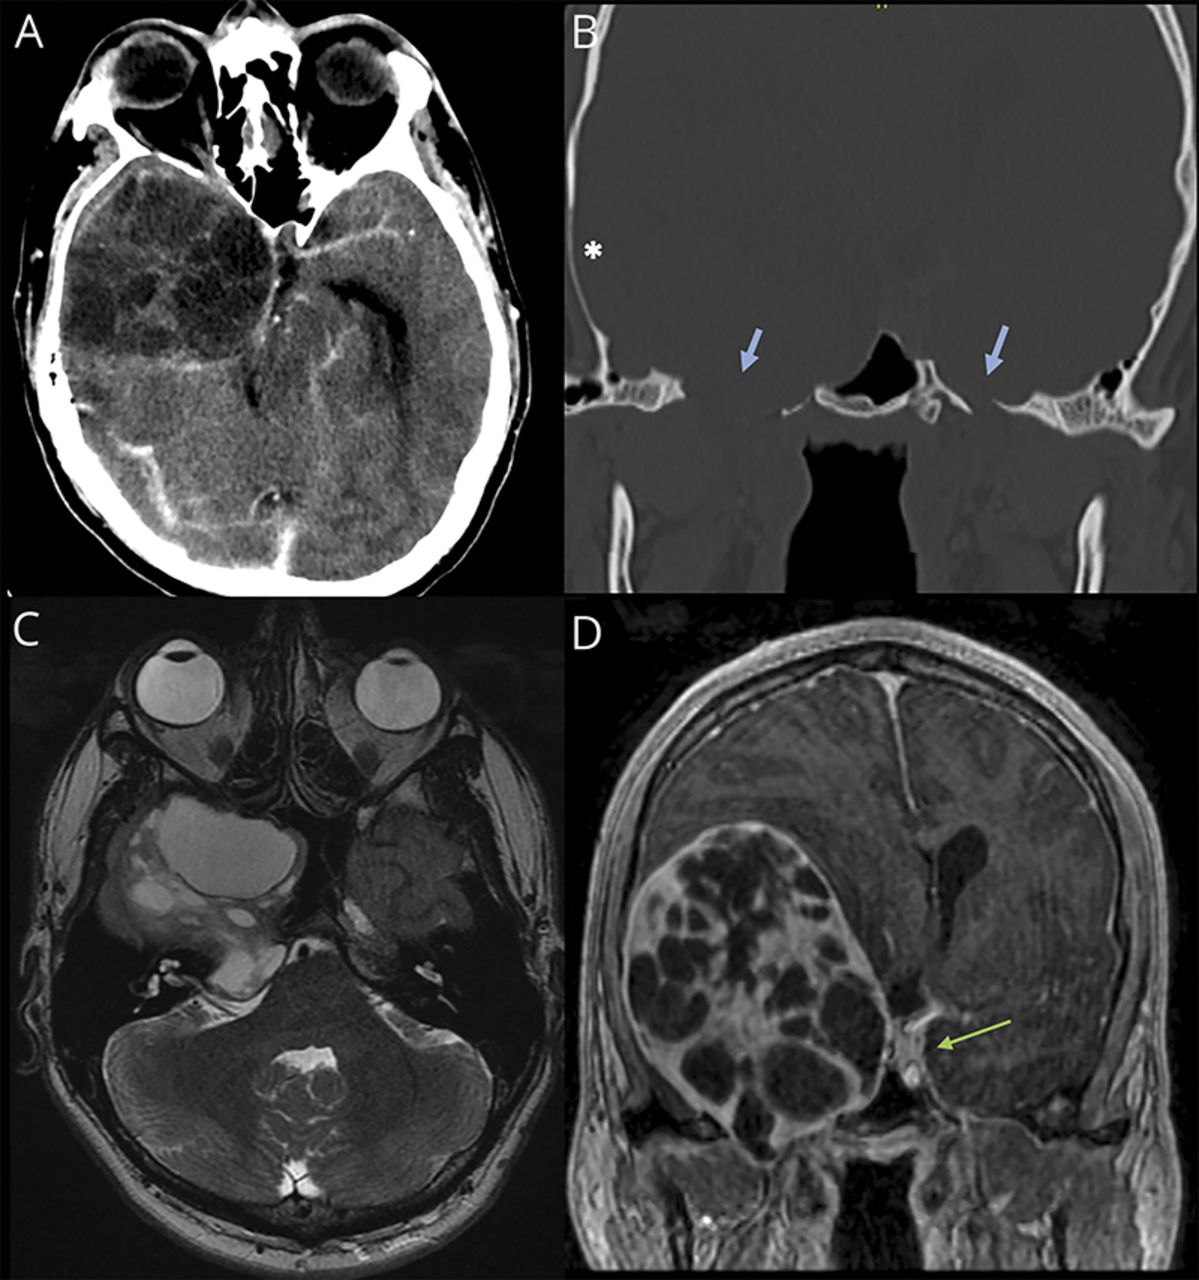

急诊CT增强头显示右额叶轴外肿物,有明显肿物效应,中线移位,伴左侧脑室压迫,基底池淤积(图2).邻近骨重塑,提示长期病变。脑部MRI增强成像进一步显示,一个巨大的多囊性边缘强化轴外肿块占据右侧中颅窝大部分区域,延伸至右侧眶尖、眶上裂、卵圆孔、海绵窦、梅克尔洞和右侧桥小脑角池,伴脑桥脑和小脑中梗受压。病人被收治到神经外科。脑电图显示中度全身性背景减慢,右半球更糟,没有任何间期癫痫样放电、癫痫发作或任何déjà vu事件被捕获。然而,基于临床原因,患者开始使用苯妥英。病变分2期切除。组织学上主要由Antoni A梭形细胞交错组成,有少量Antoni B结构区域和含铁血黄素沉积和退化灶。这与来自三叉神经的WHO I级神经鞘瘤一致。术后,患者右眼视力保持不变,而左眼视力略有改善至20/25。 He continued to have limitation of right eye abduction and occasional paresthesia involving the right hemiface. The episodes of déjà vu resolved.

图2

• 下载图

• 在新标签页打开

• 下载演示文稿

图2 CT和MRI显示一个巨大的囊性肿瘤

CT头部造影剂(A)显示右侧中颅窝大面积不均质病灶,肿块效应;骨窗(B)显示右侧邻近颅骨(星号)变薄和重塑,两侧卵圆孔标记(蓝色箭头),显示右侧肿块扩张。轴向T2 MR (C)显示不均质哑铃状多分叶肿物。冠状位T1后增强MR (D)图像显示囊性环增强肿块;绿色箭头所示为未受影响左侧海绵窦,显示肿块延伸至右侧海绵窦。